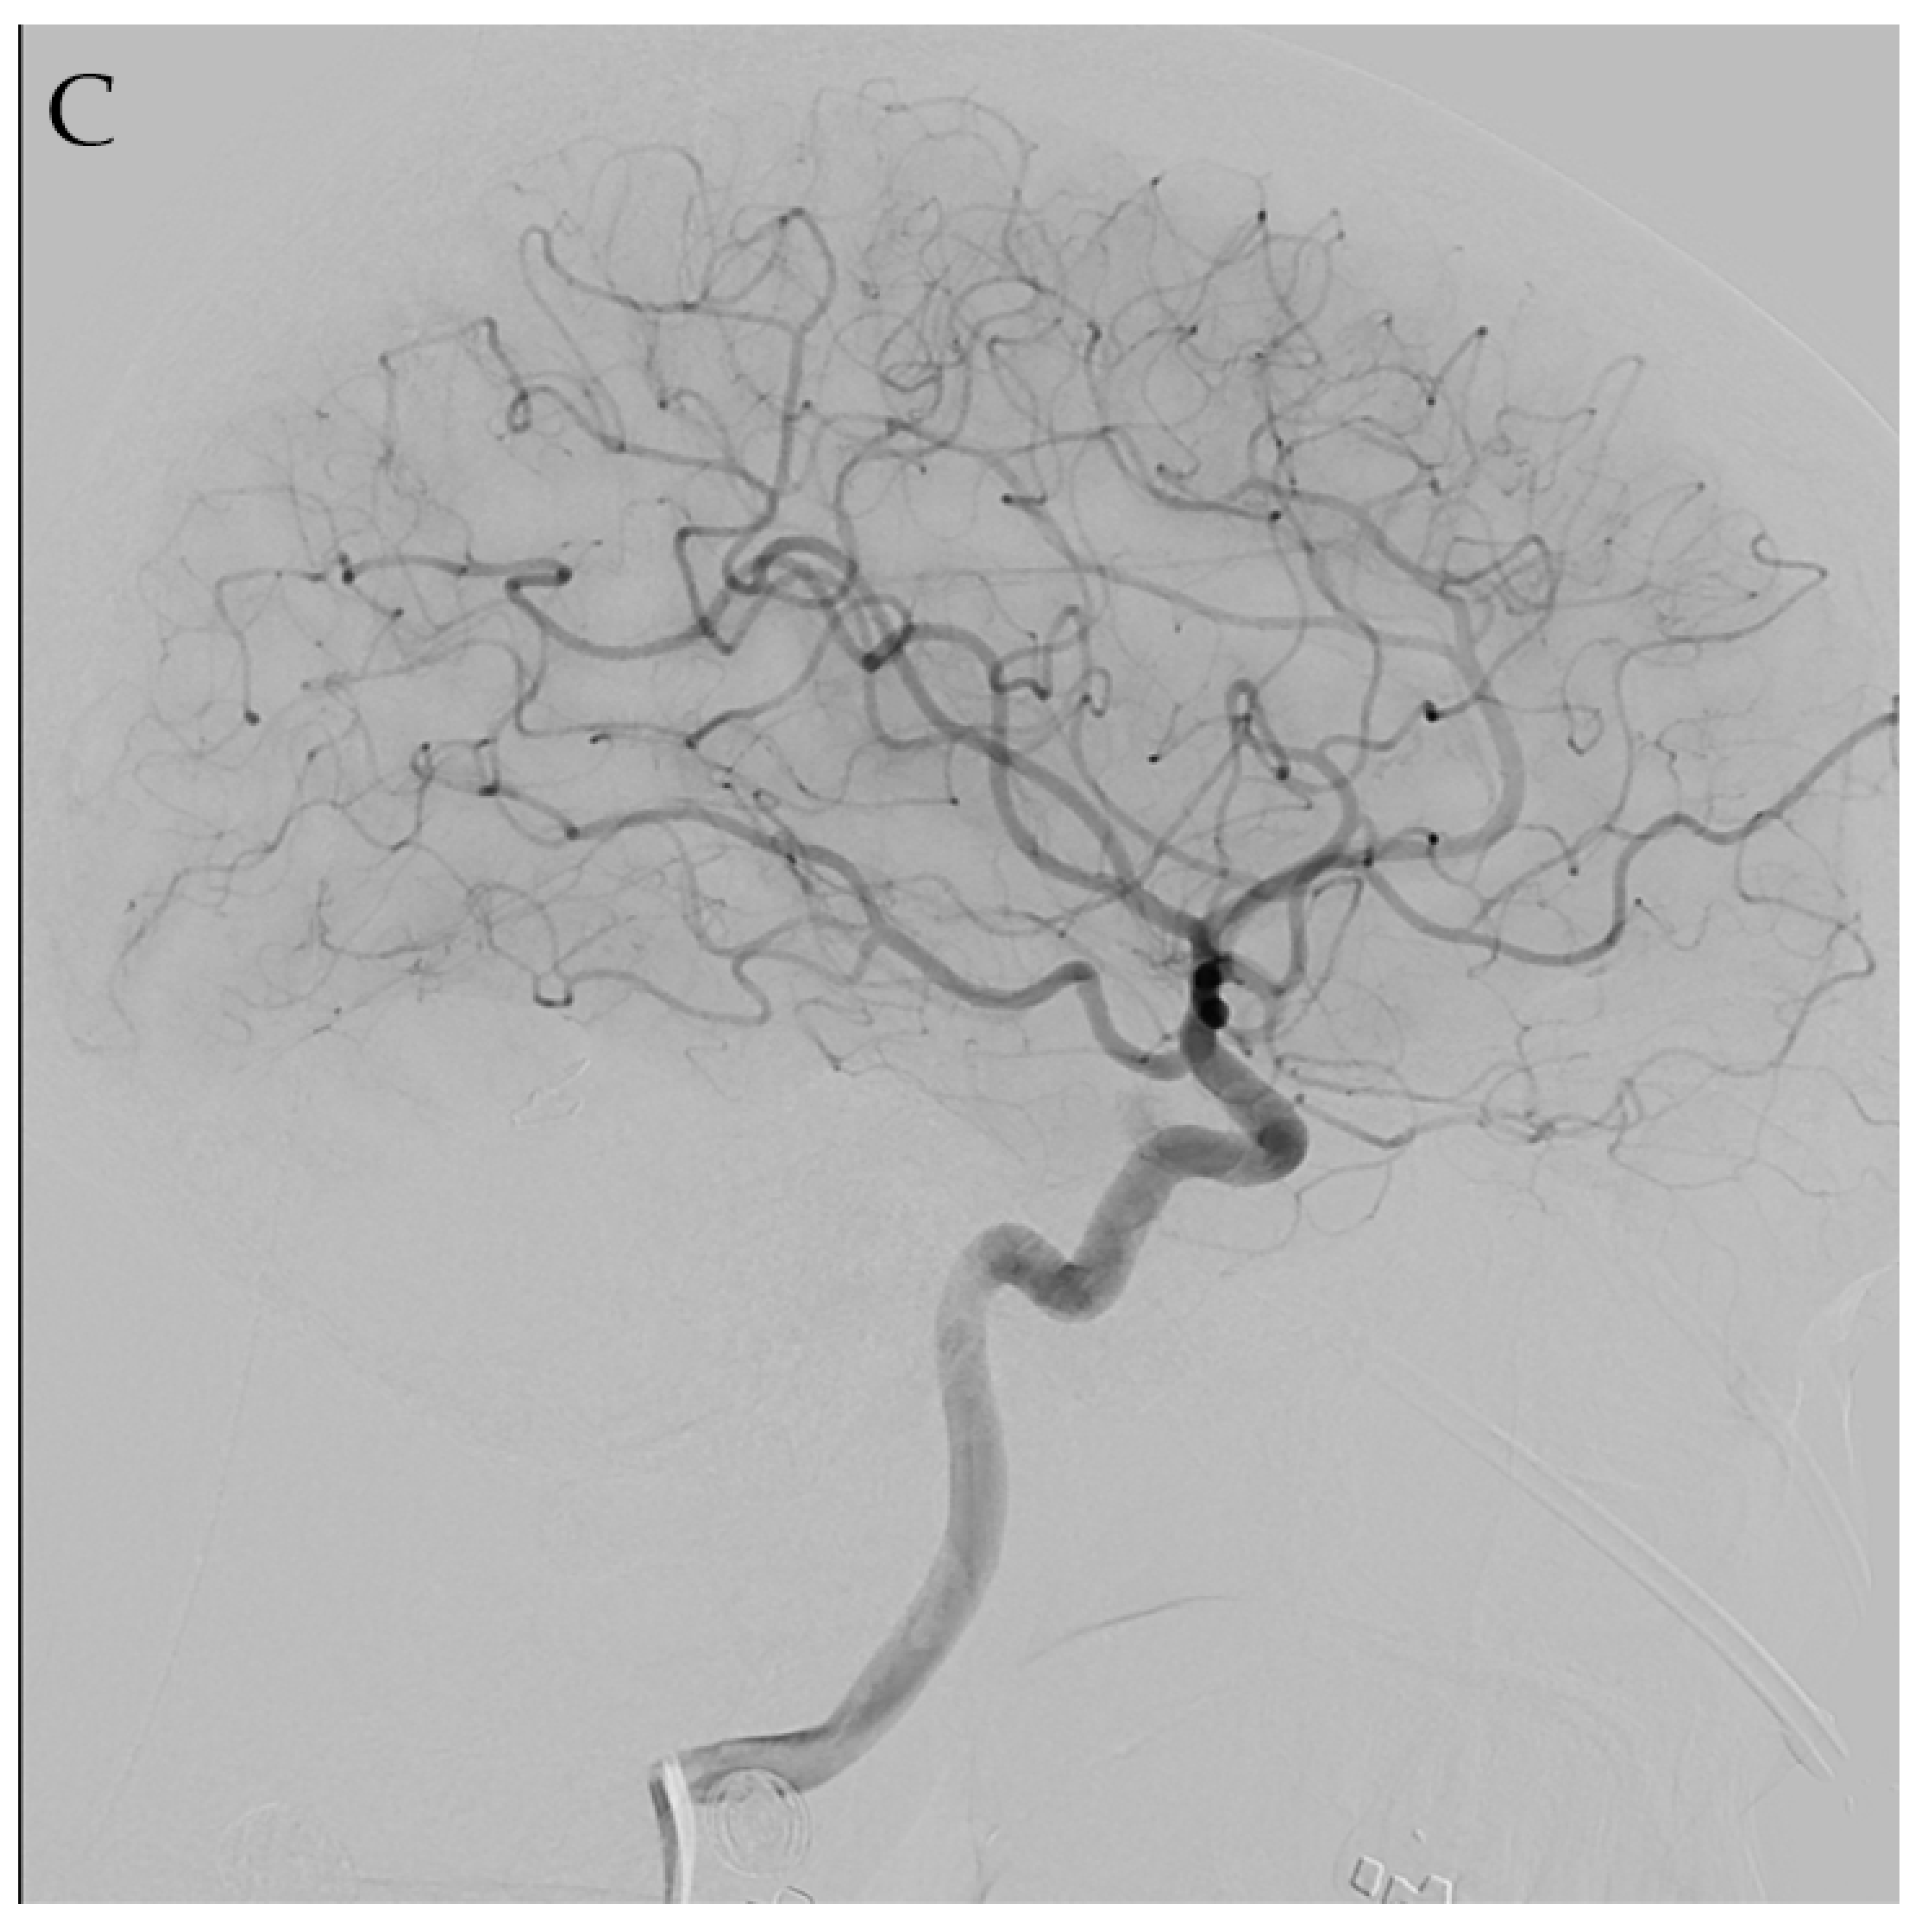

4.1. Microsurgery

4.2. Endovascular Embolization

4.3. Stereotactic Radiosurgery

4.4. Multimodality Therapy